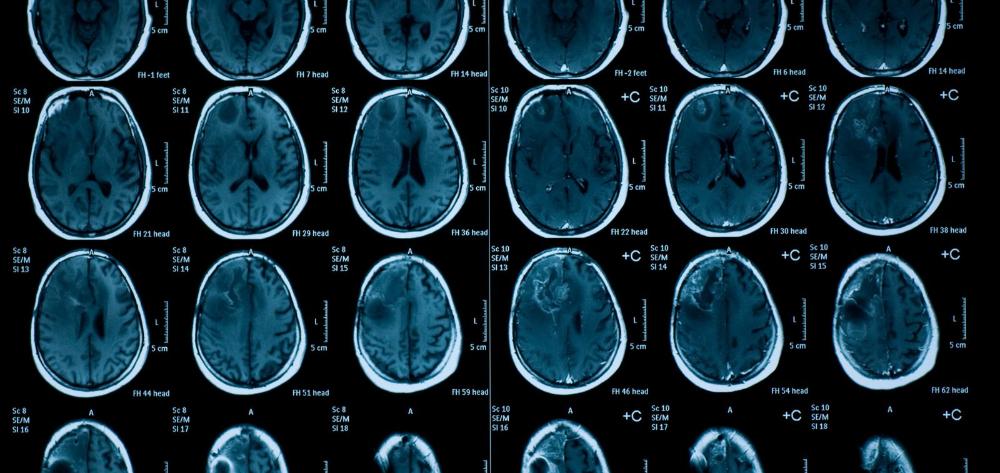

Los escáneres cerebrales realizados a más de 2.000 preadolescentes sugieren que la exposición al frío y al calor en los primeros años de vida puede tener efectos duraderos en la microestructura de la materia blanca del cerebro, especialmente cuando se vive en barrios pobres. El estudio, publicado en Nature Climate Change, pone de manifiesto la vulnerabilidad de los fetos y de la población infantil a las temperaturas extremas. Esta investigación ha sido liderada por el Instituto de Salud Global de Barcelona (ISGlobal), centro impulsado por la Fundación ”la Caixa”, y el IDIBELL, en colaboración con el Erasmus University Medical Center Rotterdam (ERASMUS MC) y el Centro de Investigación Biomédica en Red (CIBER): áreas de Epidemiología Salud Pública (CIBERESP), y Salud Mental (CIBERSAM).

En este estudio, un equipo dirigido por Guxens analizó la estructura de la sustancia blanca en el cerebro de preadolescentes para identificar ventanas de susceptibilidad a la exposición al frío y al calor en los primeros años de vida. El análisis incluyó a 2.681 niñas y niños del Estudio Generación R, una cohorte de nacimiento de Rotterdam, que se sometieron a una resonancia magnética (IRM) entre los 9 y los 12 años de edad. El protocolo de IRM evaluó la conectividad cerebral midiendo la magnitud y la dirección de la difusión del agua en la sustancia blanca del cerebro. En los cerebros más maduros, el agua fluye más en una sola dirección que en todas, lo que da valores más bajos para un marcador llamado difusividad media y valores más altos para otro marcador llamado anisotropía fraccional. El equipo de investigación utilizó un enfoque estadístico avanzado para estimar, para cada participante, la exposición a temperaturas medias mensuales desde la concepción hasta los 8 años de edad , y su efecto sobre estos parámetros de conectividad por resonancia magnética (difusividad media y anisotropía fraccional) medidos a los 9-12 años.